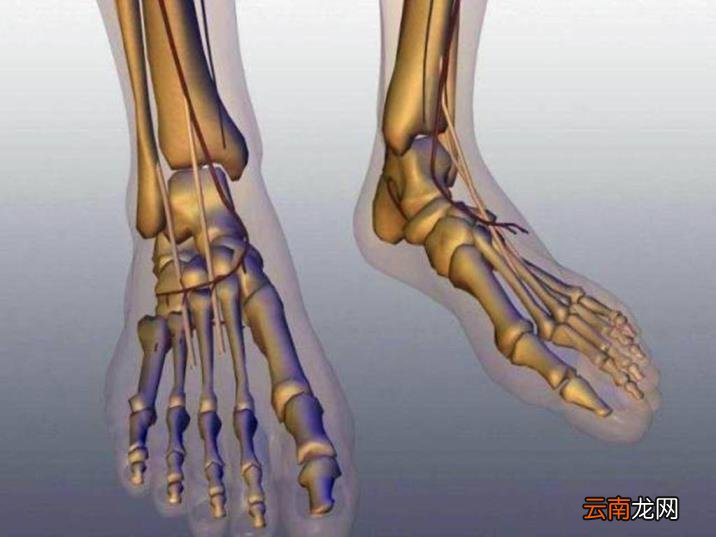

除了要忍受背痛的折磨,人类还要饱尝足痛膝伤之苦,下肢承受更多的重量,膝关节、踝关节等部位压力更大了 。

文章插图

此外,直立行走这种进化结果,也使得人类女性骨盆变窄,分娩时需要承受一定的剧痛和风险 。